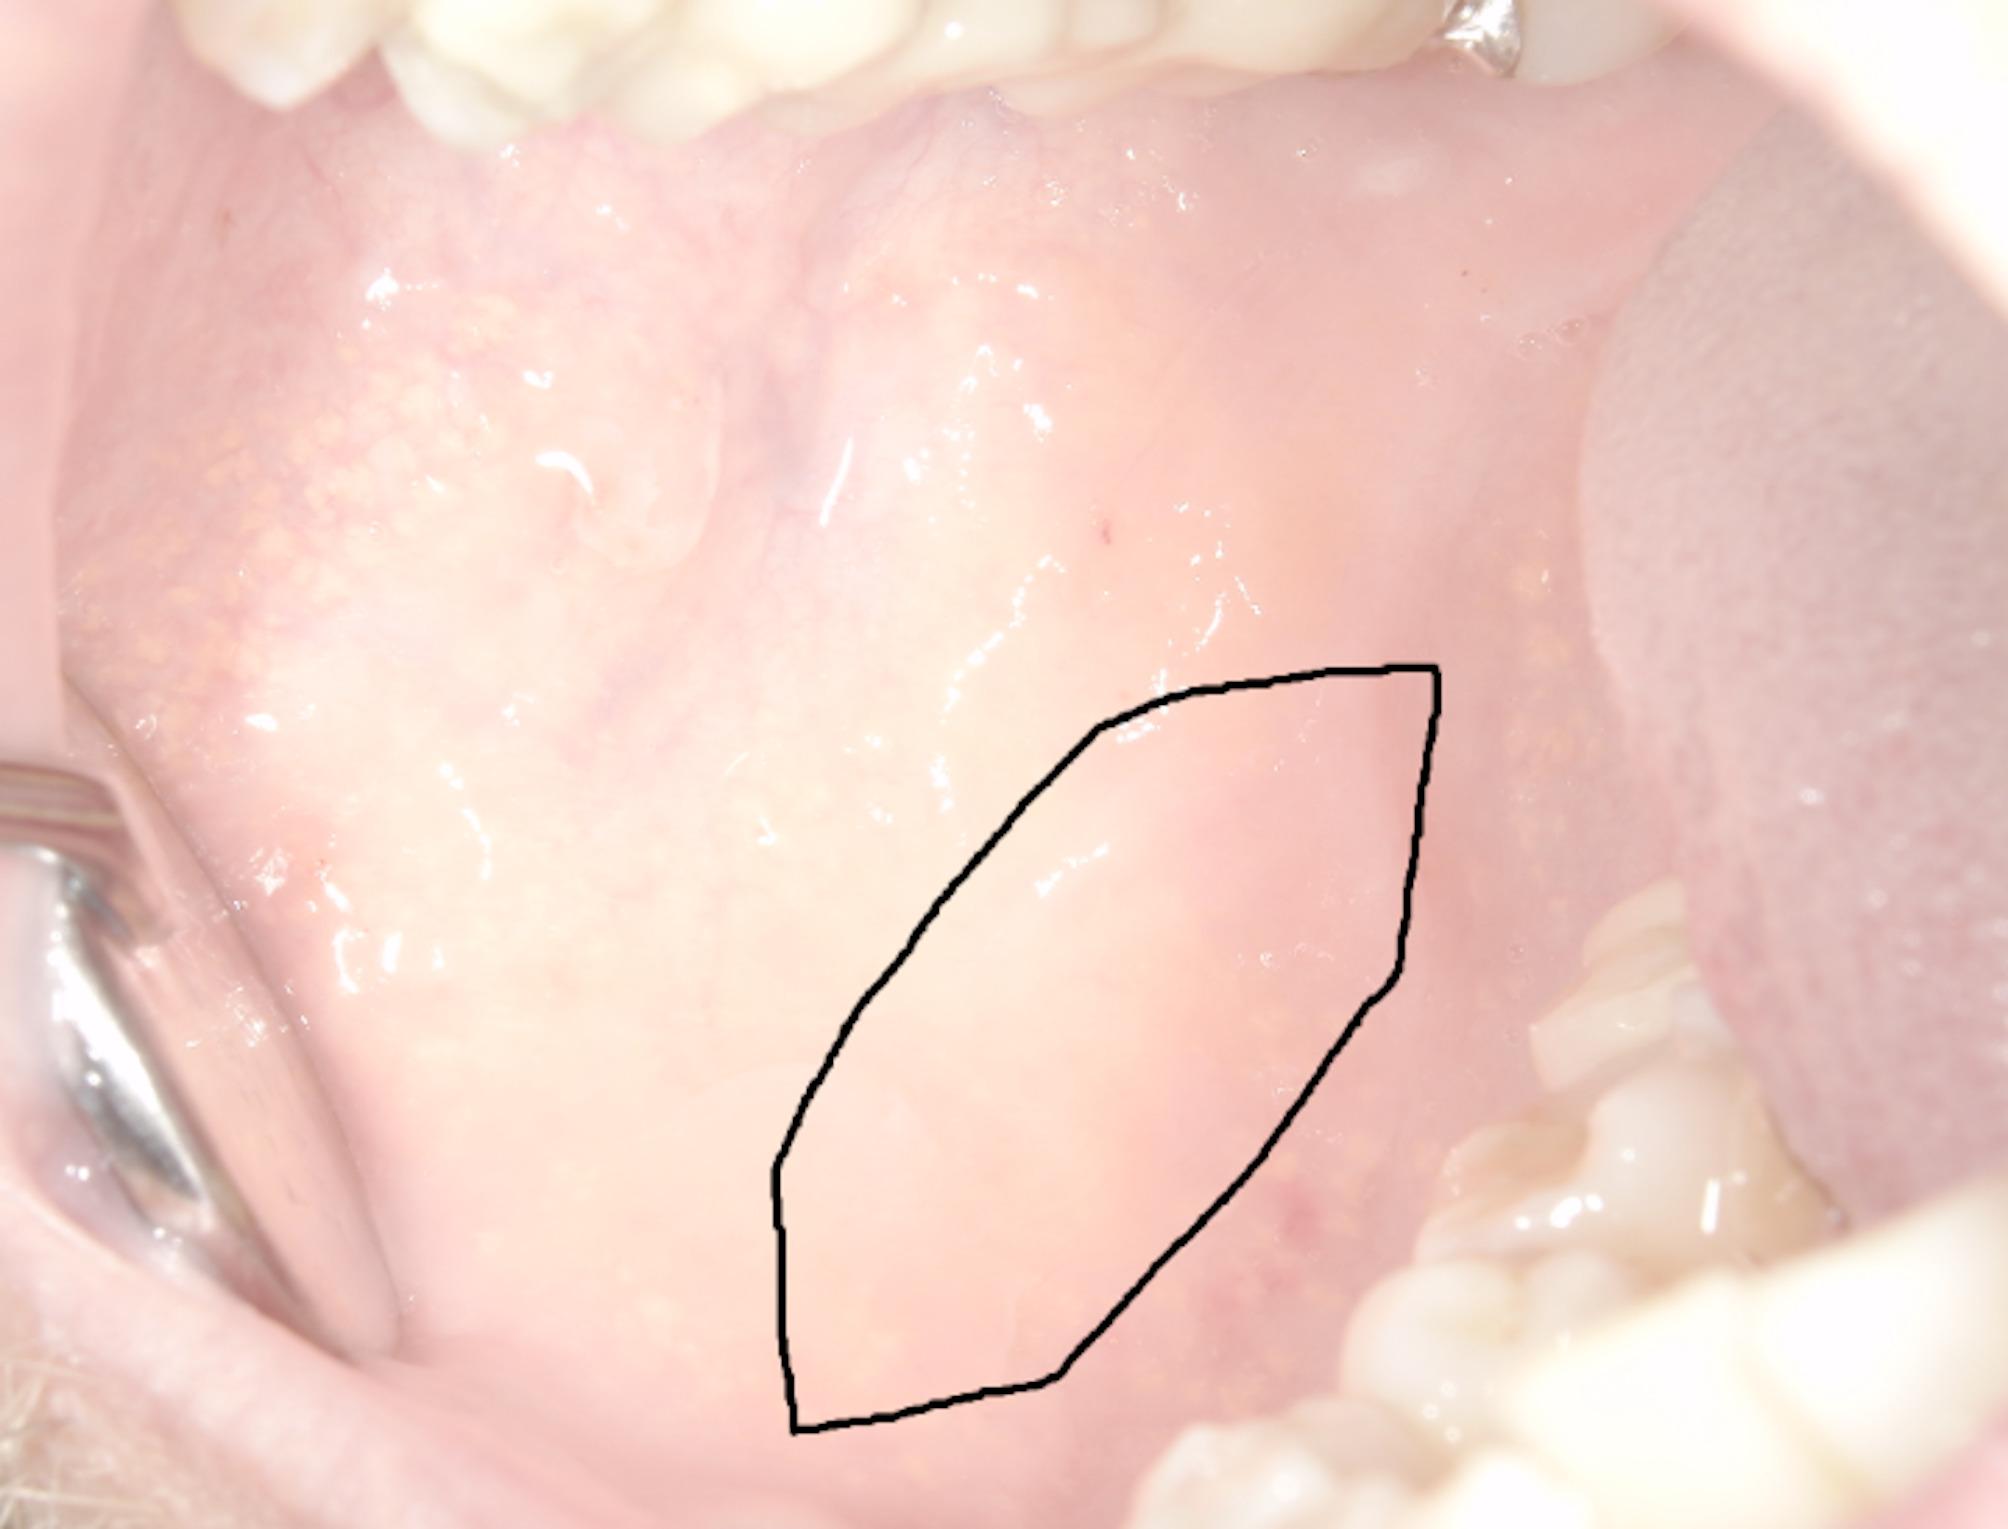

Background: Patients undergoing oral mucosa harvesting for urethroplasty may experience several challenges during recovery like scarring or changes in oral sensitivity, which can lead to long-term discomfort. In this retrospective study long-term donor site complications after harvesting of oral mucosa for urethroplasty were evaluated and a new measurement method for oral volume differences between the non-operated and operated sides was applied.

Methods: Thirty adult male patients who underwent urethroplasty with buccal mucosa grafting were included. At a median of 43 months after surgery, a standardized questionnaire was used, and clinical examinations were conducted to measure the postoperative elasticity of the buccal mucosa. This measurement compared the non-operated side with the operated side. Additionally, we examined descriptive statistics and the influence of smoking status, diabetes mellitus, immunosuppression, alcohol consumption, and graft size.

Results: In total, 36% of the patients reported persistent subjective postoperative impairments, such as tightness in the oral cavity or numbness. In all patients, a difference in buccal volume was observed between the operated side and the non-operated side. This volume difference ranged from 3 to 15 ml (mean 8.10 ml, SD ± 3.4; p < 0.001). As the size of the harvested transplant increased, the postoperative buccal volume difference also increased significantly (p < 0.001). In one patient, follow-up surgery was required due to the severity of scarring. The presence of diabetes mellitus, immunosuppressive medication, smoking status, and alcohol consumption had no statistically significant effect on postoperative buccal elasticity or mouth opening.

Conclusions: The use of buccal mucosa grafts for urethroplasty is an established procedure in urology, but the oral harvesting procedure can lead to scarring within the buccal area, which is associated with a statistically significant decrease in buccal volume compared with the non-operated site. The volume analysis was performed by applying a new measurement method, which enables, for the first time, the quantification of oral donor site morbidity.